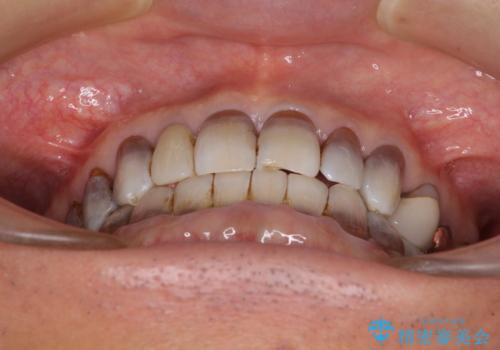

- 前歯のクロスバイトを気にして来院された患者様です。

骨格的に下顎が前方位ではありますが、歯並びが改善されれば正常咬合となることが分かったため、インビザラインを用いて咬み合わせを改善していくこととしました。